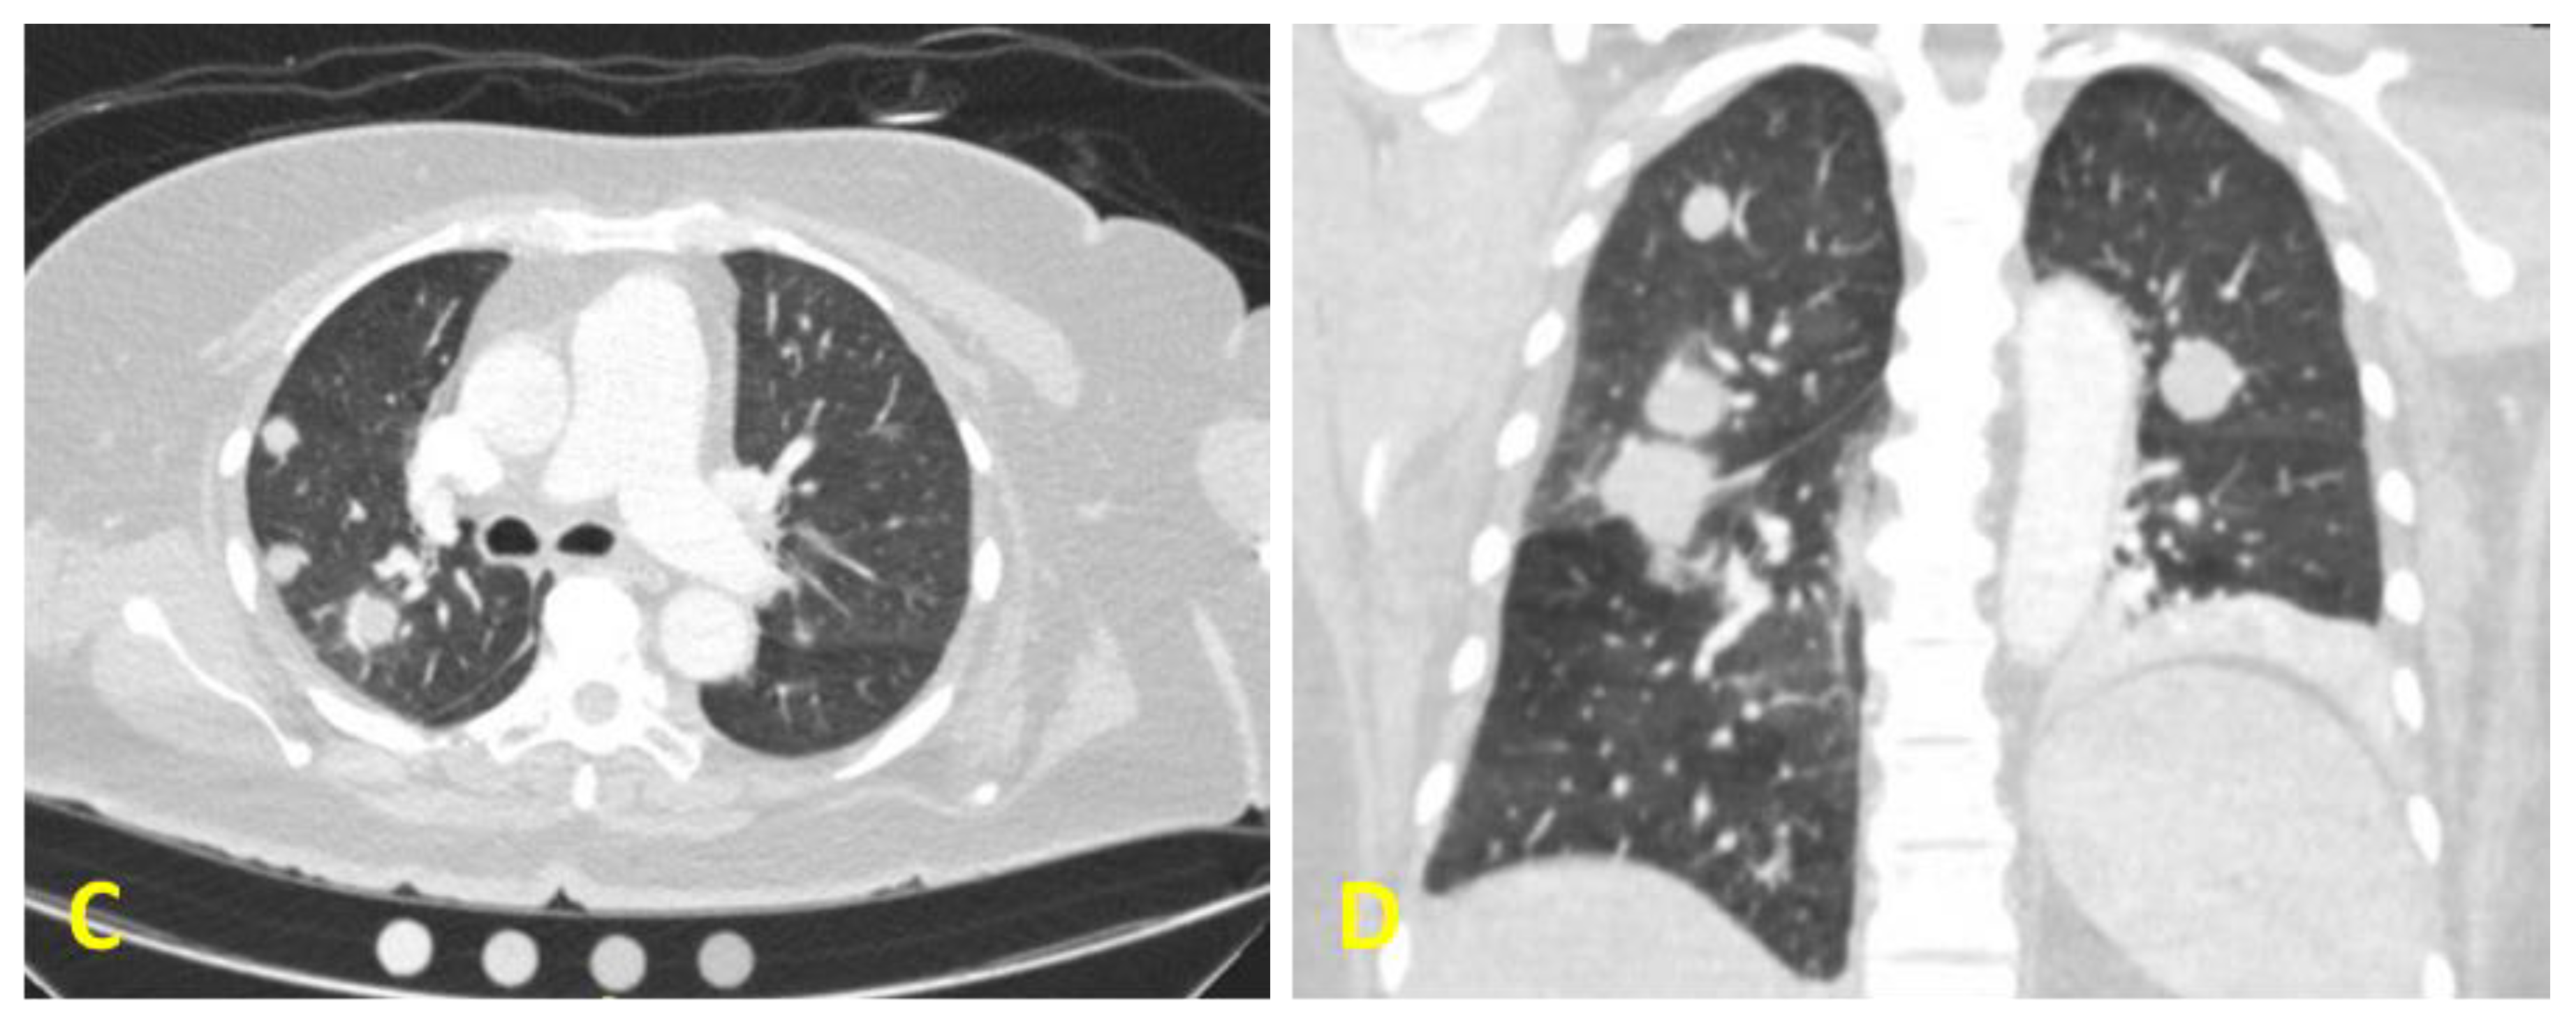

Figure 1.

Computed tomography (CT) scan of the patient’s neck showing a large mass located at the level 4, with central cystic necrosis ((A): cross section and (B): coronal section). Axial section (C) and coronal section (D) taken from a CT angiogram of the chest showing metastatic lung lesions.